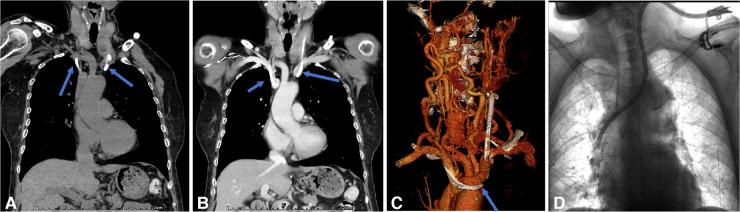

The aim of this study was to evaluate the causes of the dysfunctional tunneled cuffed catheters (TCCs) using multi-spiral computed tomography venography (MSCTV), and to analyze the outcomes of endovascular salvage techniques.

MSCTV showed a range of abnormalities in the hemodialysis (HD) patients, including central venous occlusion ( = 4), fibrin sheath formation ( = 3), malposition of the catheter tips ( = 4), central venous perforation ( = 1), thrombus formation ( = 12), regular catheter exchange without determined lesions ( = 3). Interventional catheter salvage procedures were performed, such as catheter exchange, balloon disruption of a fibrin sheath, angioplasty for central vein stenosis, and stent deployment. The technical success rate for catheter insertions was 100%, and no procedure-related severe complications were observed. The 30-day catheter patency for all assessable catheters was 85.2%.

MSCTV显示血液透析(HD)患者存在一系列异常情况,包括中心静脉闭塞(=4例)、纤维蛋白鞘形成(=3例)、导管尖端位置异常(=4例)、中心静脉穿孔(=1例)、血栓形成(=12例)、无明确病变的常规导管更换(=3例)。实施了介入性导管挽救程序,如导管更换、纤维蛋白鞘球囊破坏、中心静脉狭窄血管成形术和支架置入术。导管插入的技术成功率为100%,未观察到与操作相关的严重并发症。所有可评估导管的30天导管通畅率为85.2%。